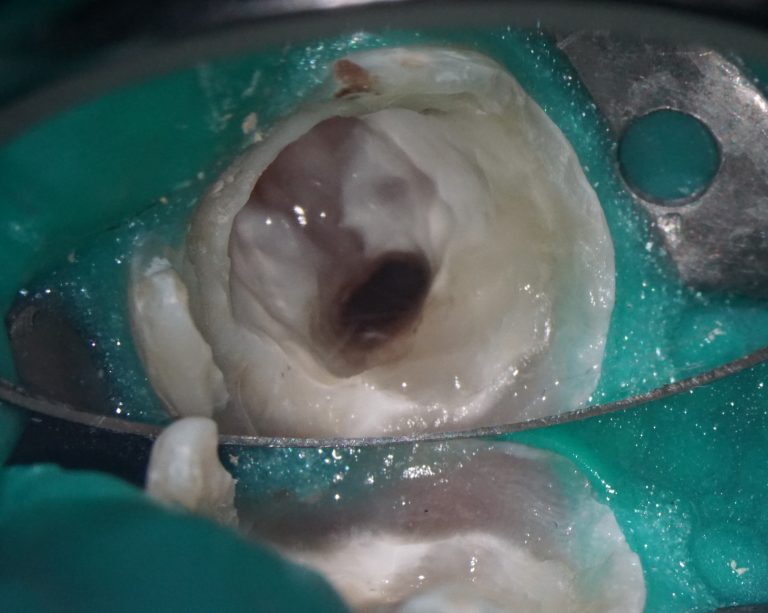

The slide illustrates the sequence of stages involved in prosthetic rehabilitation, obtaining digital impressions and uploading them to the Diagnocat STL module, to creating temporary crowns and forming the desired emergence profiles for implants

The use of Diagnocat AI in planning implant treatment improves the accuracy and predictability of the procedure, allowing the clinician to achieve the best results for the patient